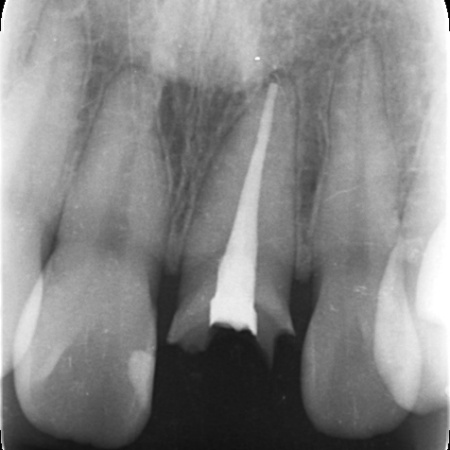

お口の中を拝見したところ、左上の前歯が大きく折れて被せ物を支える土台ごと外れていました。

レントゲン検査で確認した結果、歯の根自体には問題がなく炎症も見られなかったため、適切な治療を行えば歯を残せる状態であることが判明しました。

そこで、白いグラスファイバーを用いた土台(ファイバーコア)に白い被せ物(ジルコニアセラミッククラウン)を装着する治療を提案し、同意いただきました。

ファイバーコアと接着剤を組み合わせることで歯根と一体化させ、丈夫で長持ちする土台に仕上げました。

土台が完成したあとは歯科用顕微鏡のマイクロスコープで確認しながら、被せ物をスムーズに装着できるよう歯の形を丁寧に整えました。

後日、完成したジルコニアセラミッククラウンを装着し、治療を完了しました。